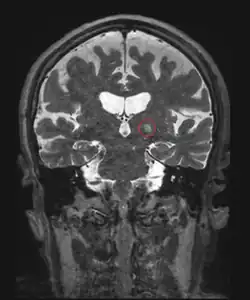

Deep Brain Stimulation (DBS)

Another invasive surgical treatment of essential tremor is deep brain stimulation (DBS). DBS is a surgical procedure that involves the placement of a permanent electrode with 4-8 contacts within the brain with connecting wires connected to a pulse stimulator implanted near the patient's collarbone.[65] In the treatment of tremor, the electrodes are placed in the ventral intermediate nucleus (Vim) of the thalamus.

The pulse stimulator delivers constant electrical pulses to the target area, which interfere with activity of the target area, which has been shown to improve tremor symptoms.[91] At one year following the surgical intervention with DBS, patients showed 66% improvement and 48% improvement at 10 years.[80] DBS is considered an effective surgical treatment of ET, but there are associated side effects and complications that have been reported with DBS in clinical trials, including imbalance or gait instability, dystonia, paresthesia, hemorrhage.[79]